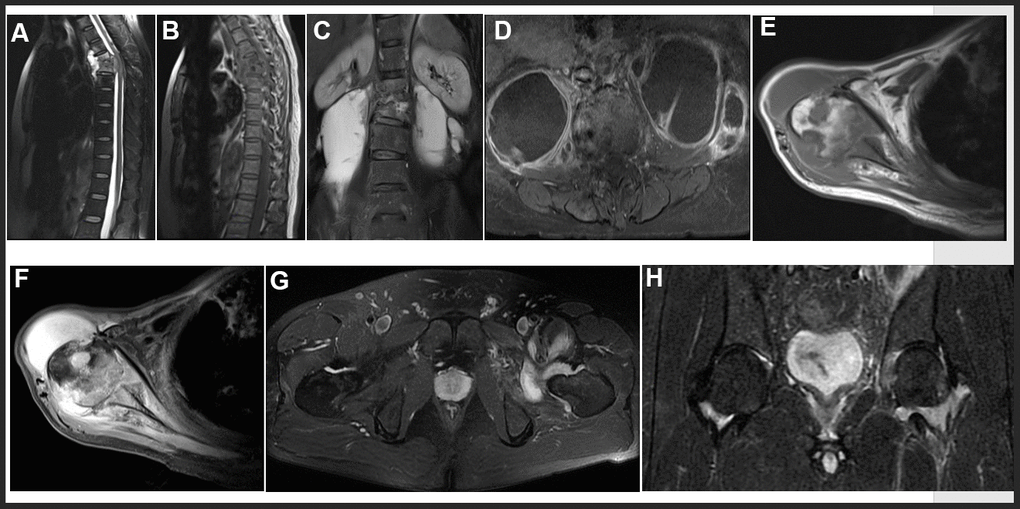

MRI features in our study included intervertebral disc destruction (Figure 3A, 3B), para- or intra-osseous abscess (Figure 3A, 3B), subligamentous spread, psoas abscess (Figure 3C, 3D), worm like destruction (Figure 3E, 3F), and synovitis and synovial fluid (Figure 3G, 3H).

Figure 3. Representative examples of MRI in OTB patients. (A, B) Thoracic spine tuberculosis: showing destruction of vertebral and paravertebral abscess. (C, D) Lumbar spine tuberculosis: showing destruction of vertebral and psoas abscess. (E, F) Right shoulder tuberculosis: showing worm like destruction of the right humeral head with effusion in the articular cavity. (G, H) Left hip joint tuberculosis: showing left hip joint synovitis and synovial fluid.